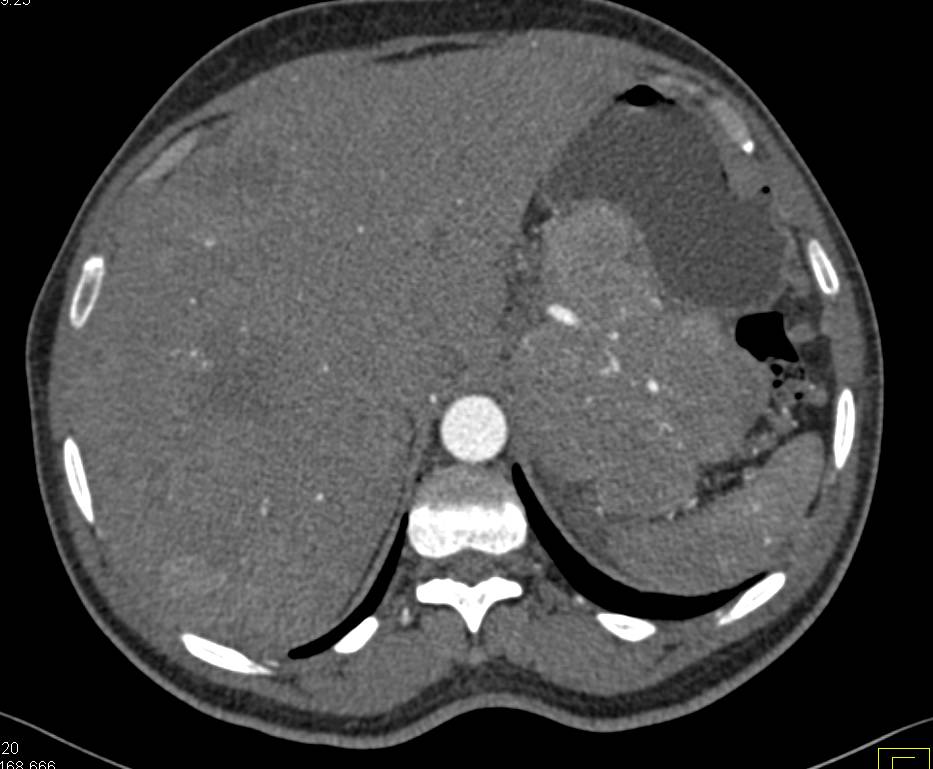

Metastatic Neuroendocrine Tumor Tail of Pancreas